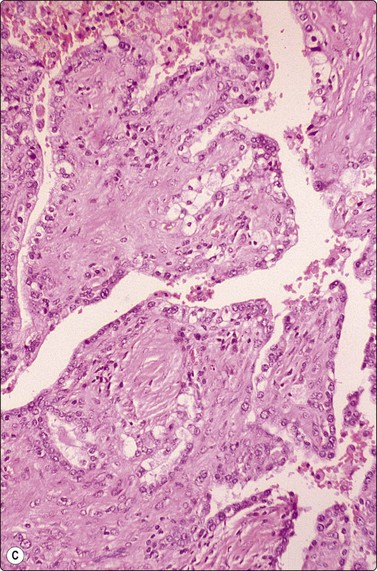

image

Fig. 8.20 Well-differentiated adenocarcinoma

Lepidic growth pattern. Tissue section (H&E, MP).

Fig. 8.21 Well-differentiated adenocarcinoma

Monolayered sheet of glandular cells with honeycombing and prominent mucin (Pap, HP).

Fig. 8.22 Well-differentiated adenocarcinoma

Mucinous with lepidic growth pattern. Tissue section (H&E, MP).

The cellular morphology of adenocarcinoma is similar to that described in brush material. Rosettes, acinar formations or cohesive cell clusters (Figs 8.18 and 8.19) represent anatomical structures removed from the tumor by the needle. The larger the gland formations, the less likely they are to be removed intact and, when only partly removed, deposit on the slide as flat sheets in a monolayer (Fig. 8.18): a useful indicator of glandular differentiation. Artifactual spaces are often seen in large tissue fragments and may be misinterpreted as acinar structures; however, where the spaces have an ‘anatomical’ rigidity, they may indicate glandular differentiation. Mucin secretion is difficult to identify without the aid of special stains, and vacuolation of the cytoplasm may occur as a result of degeneration or the presence of glycogen. In H&E- or Pap-stained material vacuoles with a central, inspissated, eosinophilic or orangiophilic center are very suggestive of mucin secretion and correspond to the intracellular lumina described ultrastructurally in adenocarcinomas. With MGG staining, mucin may be visible as magenta or purple material within the cytoplasm, either homogeneously or as red granules within a pale vacuole. Well-formed columnar cells or groups of palisaded cells may be a guide to glandular differentiation and terminal plates/bars may also be present. In the 2004 WHO classification,217 the definition of BAC was limited to a non-invasive process and is now an uncommon diagnosis, requiring full histological assessment; there is currently debate as to whether the term should be used at all, especially since a diagnosis of BAC cannot be rendered on small biopsy samples or cytological samples. However, it is still possible to suggest that a tumor may have a BAC-like component based on cytological features. These include large, cohesive, monolayered sheets which reflect the growth of neoplastic cells in a monolayer along alveolar walls, papillary processes, cell balls and clusters, intranuclear cytoplasmic inclusions and psammoma bodies (Figs 8.18-8.22). The radiogical appearance of a purely ground-glass opacity without a solid component is also suggestive of a BAC.